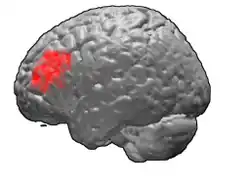

Brodmann area 46

Brodmann area 46, or BA46, is part of the frontal cortex in the human brain. It is between BA10 and BA45.

BA46 is known as middle frontal area 46. In the human brain it occupies approximately the middle third of the middle frontal gyrus and the most rostral portion of the inferior frontal gyrus. Brodmann area 46 roughly corresponds with the dorsolateral prefrontal cortex (DLPFC), although the borders of area 46 are based on cytoarchitecture rather than function. The DLPFC also encompasses part of granular frontal area 9, directly adjacent on the dorsal surface of the cortex.

Animation.